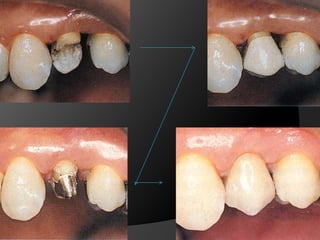

CORONA COMPLETA METAL-CERÁMICA: Iguales indicaciones que la metálica pero  estética

CORONA TOTALMENTE CERÁMICA: Combinación de recubrimiento completo y máxima estética. La eliminación de estructura dentaria es mayor.

CORONAS DE RECUBRIMIENTO COMPLETOMetal Cerámica: Son una combinación de 	un material cerámico de recubrimiento y 	una subestructura metálicaEn los años 50s se desarrolló la primera aleación oro-porcelana comercialmente exitosa

CORONAS DE RECUBRIMIENTO COMPLETOMetal Cerámica: Capa delgada de porcelana opacaPorcelana de CuerpoPorcelana Translúcida

CORONAS DE RECUBRIMIENTO COMPLETOMetal Cerámica: Metal: Grosor de 0,3 mm a 0,5 mmCerámica: Grosor 1mm aprox.